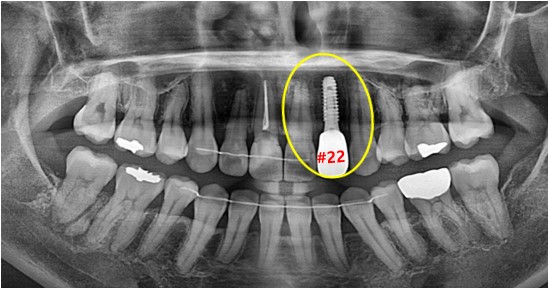

먼저 초진 구강 사진과 파노라마사진을 보도록 할게요.

먼저 파노라마 사진 속 표시된 곳을 보시면 신경치료 이후 크라운까지 씌우신 모습입니다.

두 사진으로 보시면 잇몸 쪽의 염증을 확인할 수 있습니다.

그럼 자세히 보면 뿌리 끝 쪽에 검은 공간이 보이는데 '치근 낭종' 이 있다는 것을 확인할 수 있습니다.

#22 치아는 이미 타치과에서 신경치료 + 크라운 치료가 완료된 치아였습니다.